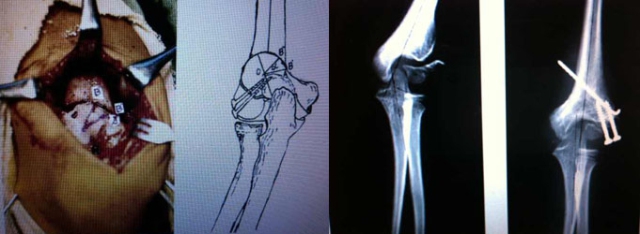

老师:手术目的包括“促进不愈合处愈合+肘外翻畸形矫正”,我会做骨折处的原位加压融合+低位肱骨髁上截骨。一个很重要的原则就是不要做切开复位,不要为了试图做切开复位而过度显露剥离不愈合处,否则可能会严重影响骨块的血运,因为肱骨外髁骨块血供主要来自于后方。

老师:文献核心是对移位不大的外髁骨折不愈合行原位加压以促进愈合,同时做内侧“闭合楔形”截骨纠正肘外翻。肘外翻畸形主要于冠状面,侧方入路就能很好显露,术中用克氏针定位指示截骨方向与水平,似乎没有必要用暴露和损伤相对较大的后侧入路,后方入路发生术后肘关节功能障碍的风险相对较高。因此,我还是习惯采用侧方入路。另外,对于肘内翻畸形的矫正有很多种术式,有研究发现,术式越复杂,术后并发症的风险越高。

学生:做髁上截骨矫形,您会怎么固定?Slongo谈到利用单臂外固定架固定,可以吗?

老师:对于小年龄儿童我会用克氏针固定,青少年可以采用钢板固定。Slongo利用单臂外架行创伤后肘内翻截骨矫形的固定,对三维畸形(冠状面内翻、矢状面前倾丢失、水平面内旋)的纠正可能更有优势。外髁骨折后肘外翻更多是单平面畸形。